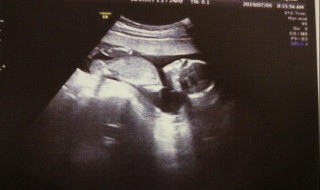

1、所谓的NT检查实际上是颈后透明带的扫描,NT检查是评估宝宝是否患有唐氏综合症的方法,它是一种筛查。NT检查筛查只能评估宝宝是否患有唐氏综合征的风险,并不能给出诊断结果。

2、NT值(颈项透明层)是指胎儿颈后皮下组织液内液体积聚的厚度当颈项透明层大于或等于2.5毫米时,可判断为颈项透明层增厚,颈项透明层增厚程度与胎儿异常的关系十分密切。颈项透明层增厚越明显,胎儿异常机会就越高,异常程度也越严重。